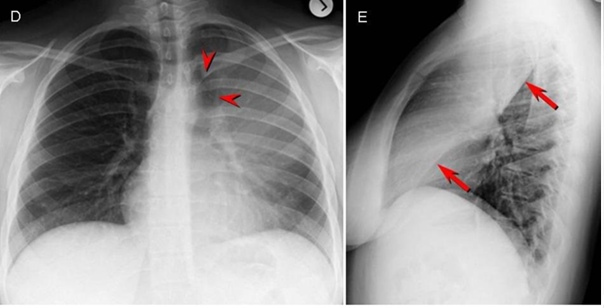

Ателектаз на рентгене грудной клетки: примеры и пояснения